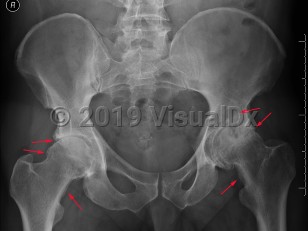

Osteoarthritis is a progressive, degenerative joint disease caused by destruction of joint cartilage and subsequently underlying bone. It is the most common form of arthritis and is thought to be caused by biochemical changes and biomechanical stresses affecting articular cartilage with ongoing use. Common areas of occurrence are the hands, spine, hips, and knees.

Although most patients present with joint pain, stiffness (limited range of motion), tenderness, and lack of flexibility, the age of presentation and temporal progression of disease is variable, driven in part by use / overuse. Joint bones may rub against each other, creating a grating sound, or small bone fragments may form spurs in the joints. Factors affecting deterioration of joint cartilage are older age, obesity, certain occupations, family history, and congenital bone malformations. Associated illnesses are diabetes, gout, and rheumatoid arthritis.